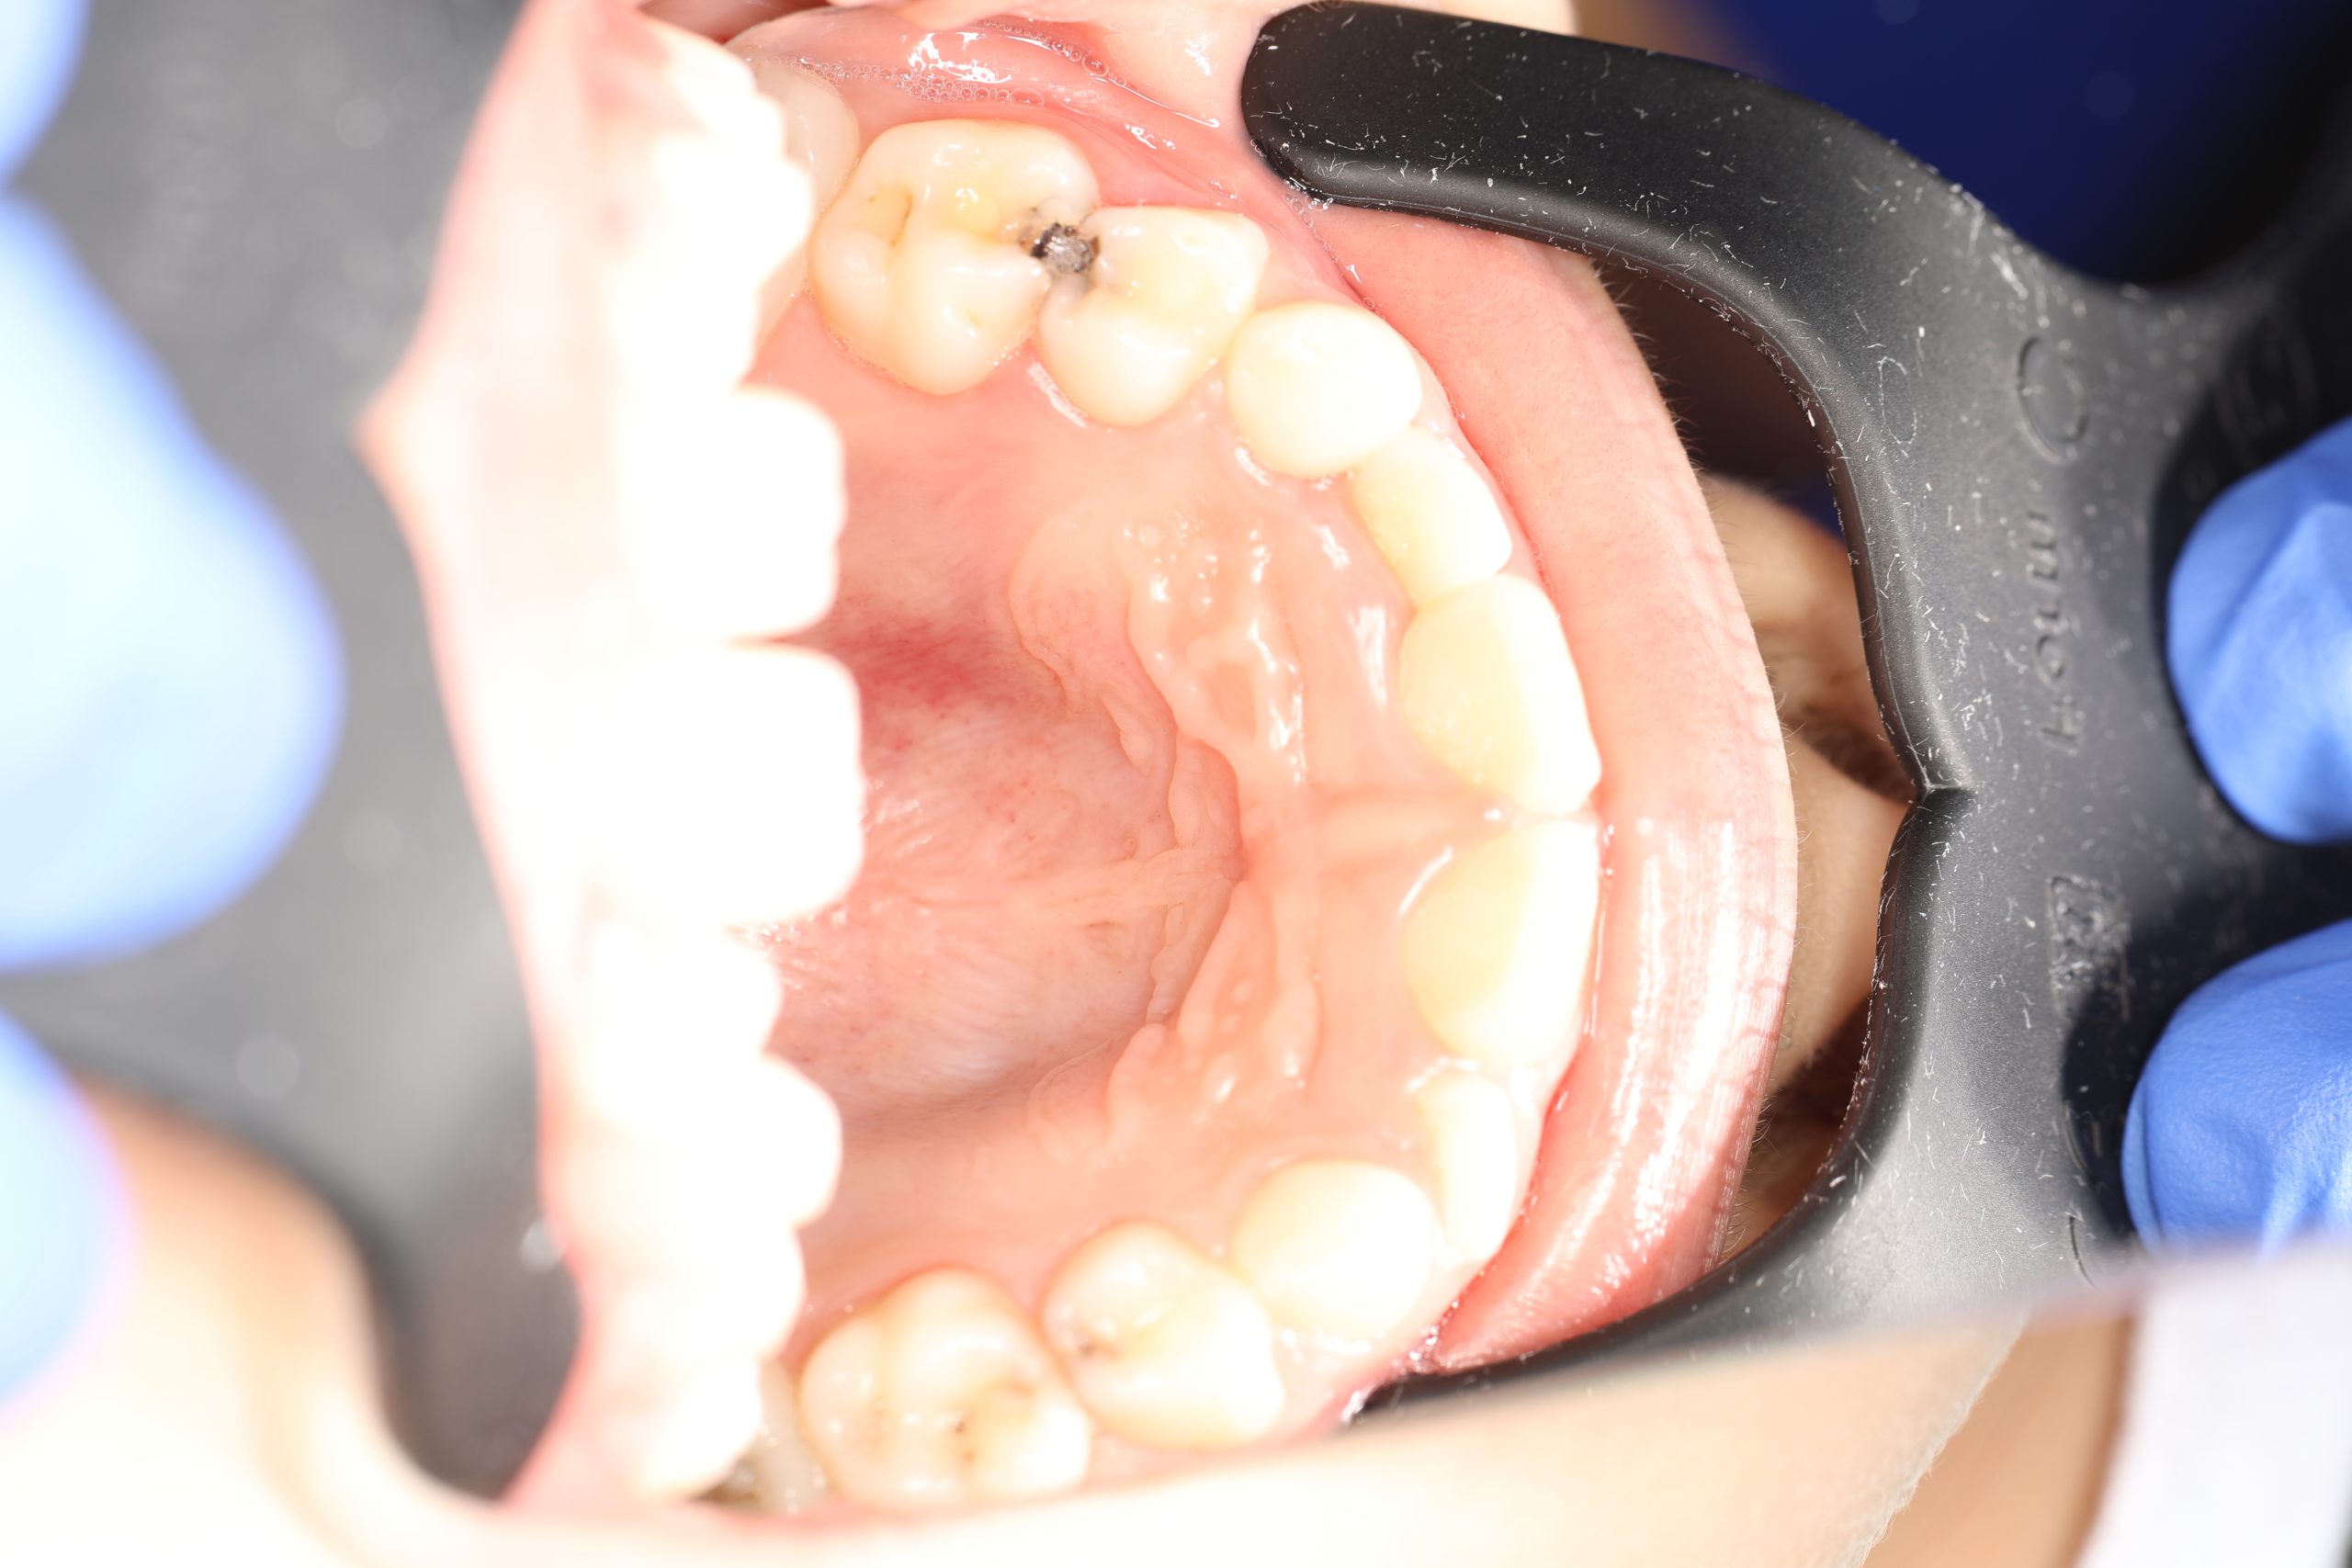

Stainless Steel Crowns (SSC)

The most popular type for back baby teeth. Durable, cost-effective, and fast to place, they provide excellent protection against further decay.

- Examination and Diagnosis: We assess the tooth to confirm that a crown is needed.